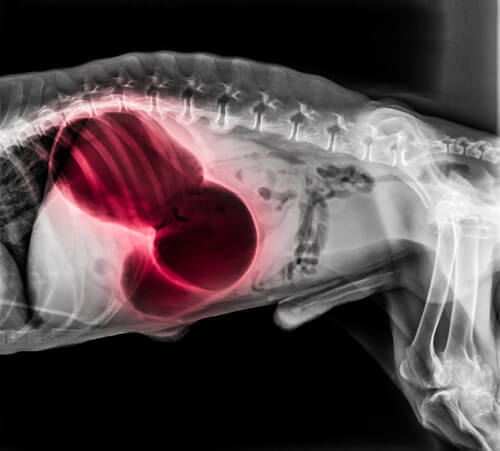

S’il se produit dans la région du cœur ou des poumons

Dans ces zones, un caillot peut entraîner divers symptômes systémiques très graves. Il peut s’agir d’évanouissements, d’essoufflement et de paralysie. Des gencives pâles ou bleues, une incapacité à dormir ou des crachats de sang peuvent se produire. La thromboembolie pulmonaire est généralement mortelle.